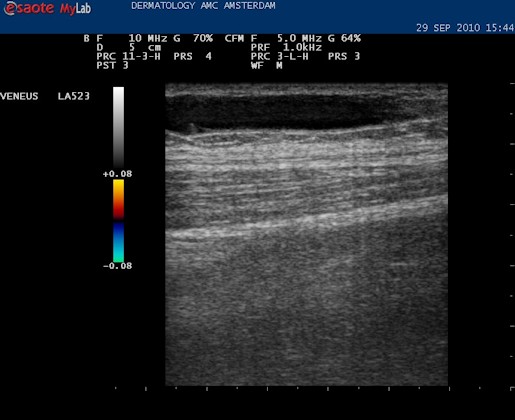

| Video: vena saphena magna op de normale diepte, liggend tussen twee fasciebladen. De VSM wordt eerst opgezocht, in het midden geplaatst en dan wordt de echokop in de lengte richting gedraaid. |

| Het is mogelijk om de diameter op te meten van het vat. Het kan handig zijn om dat te weten in verband met de therapie; of er bijvoorbeeld een VNUS catheter doorheen kan. |

| Met de duplex kan ook de reflux over het vat worden gemeten. |